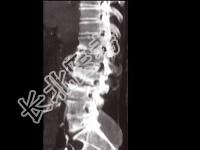

- 单项选择题男,65岁, 腰背部疼痛1月余,结合图像, 最可能的诊断是 ( )

A、脊椎结核

B、椎体压缩骨折

C、脊椎退行性变

D、脊椎转移瘤

E、L2~L3椎间盘炎